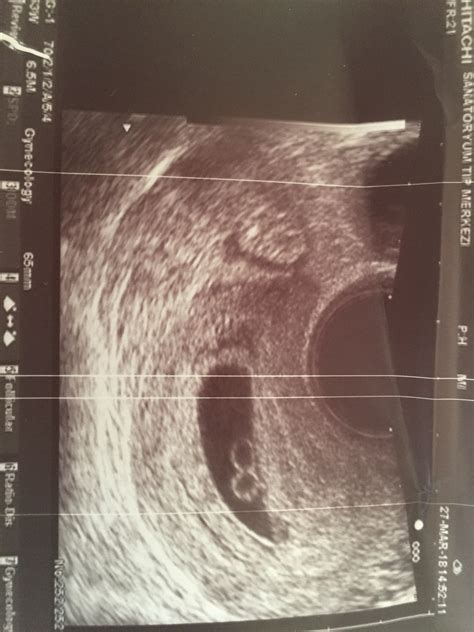

During the 8 Week Ultrasound Twins scan, a transvaginal ultrasound is usually performed. This involves inserting a small probe into the vagina to get a clearer image of the uterus and the developing embryos. The procedure is generally painless, but some women may experience slight discomfort. The ultrasound technician will apply a gel to the probe to enhance the image quality.

• Confirmation of Twins: The technician will look for two separate gestational sacs, each containing an embryo. This confirms the presence of twins.

• Type of Twins: Identical twins share a single placenta and amniotic sac, while fraternal twins have separate placentas and amniotic sacs. The ultrasound can help determine the type of twins.

• Heartbeat Detection: At 8 weeks, the embryos' heartbeats should be detectable. The technician will listen for two distinct heartbeats to ensure both embryos are developing normally.

• Measurement of Embryos: The size of the embryos will be measured to ensure they are growing at an appropriate rate. This helps in estimating the due date and monitoring the pregnancy's progress.